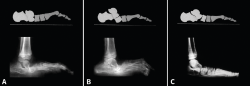

Figura 3. A: pie plano astrágalo vertical. Inflexión en la articulación talonavicular; B: pie plano paralítico. Inflexión en la articulación navículo-cuneiforme medial; C: inflexión en todas las articulaciones del arco interno: talonavicular, navículo-cuneiforme medial, primera articulación tarsometatarsiana.

En el pie plano, el doble movimiento de rotación en sentido inverso que se produce conlleva que en la columna interna del pie se produzca algún tipo de subluxación o luxación. La localización de esta tendrá relación con la etiología de cada pie plano(6): en el pie plano astrágalo vertical se produce a nivel de la talonavicular, en el pie paralítico (secuelas de poliomielitis) a nivel de la articulación navículo-cuneiforme y, en los pies planos laxos infantiles, en todas las articulaciones de la columna interna del pie: talonavicular, navículo-cuneiforme y 1.ª ATMT (Figura 3).